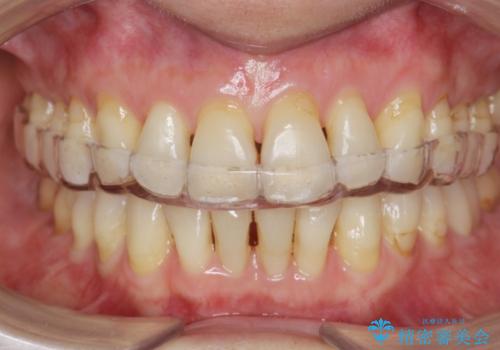

型取り(上下)をして自費のナイトガードを作製しました。

保険のナイトガードと比べると割れにくくて、噛み合わせの歯と調整を行うために歯が変に負担がかかる事なく歯ぎしりや歯の破折を予防することができます。